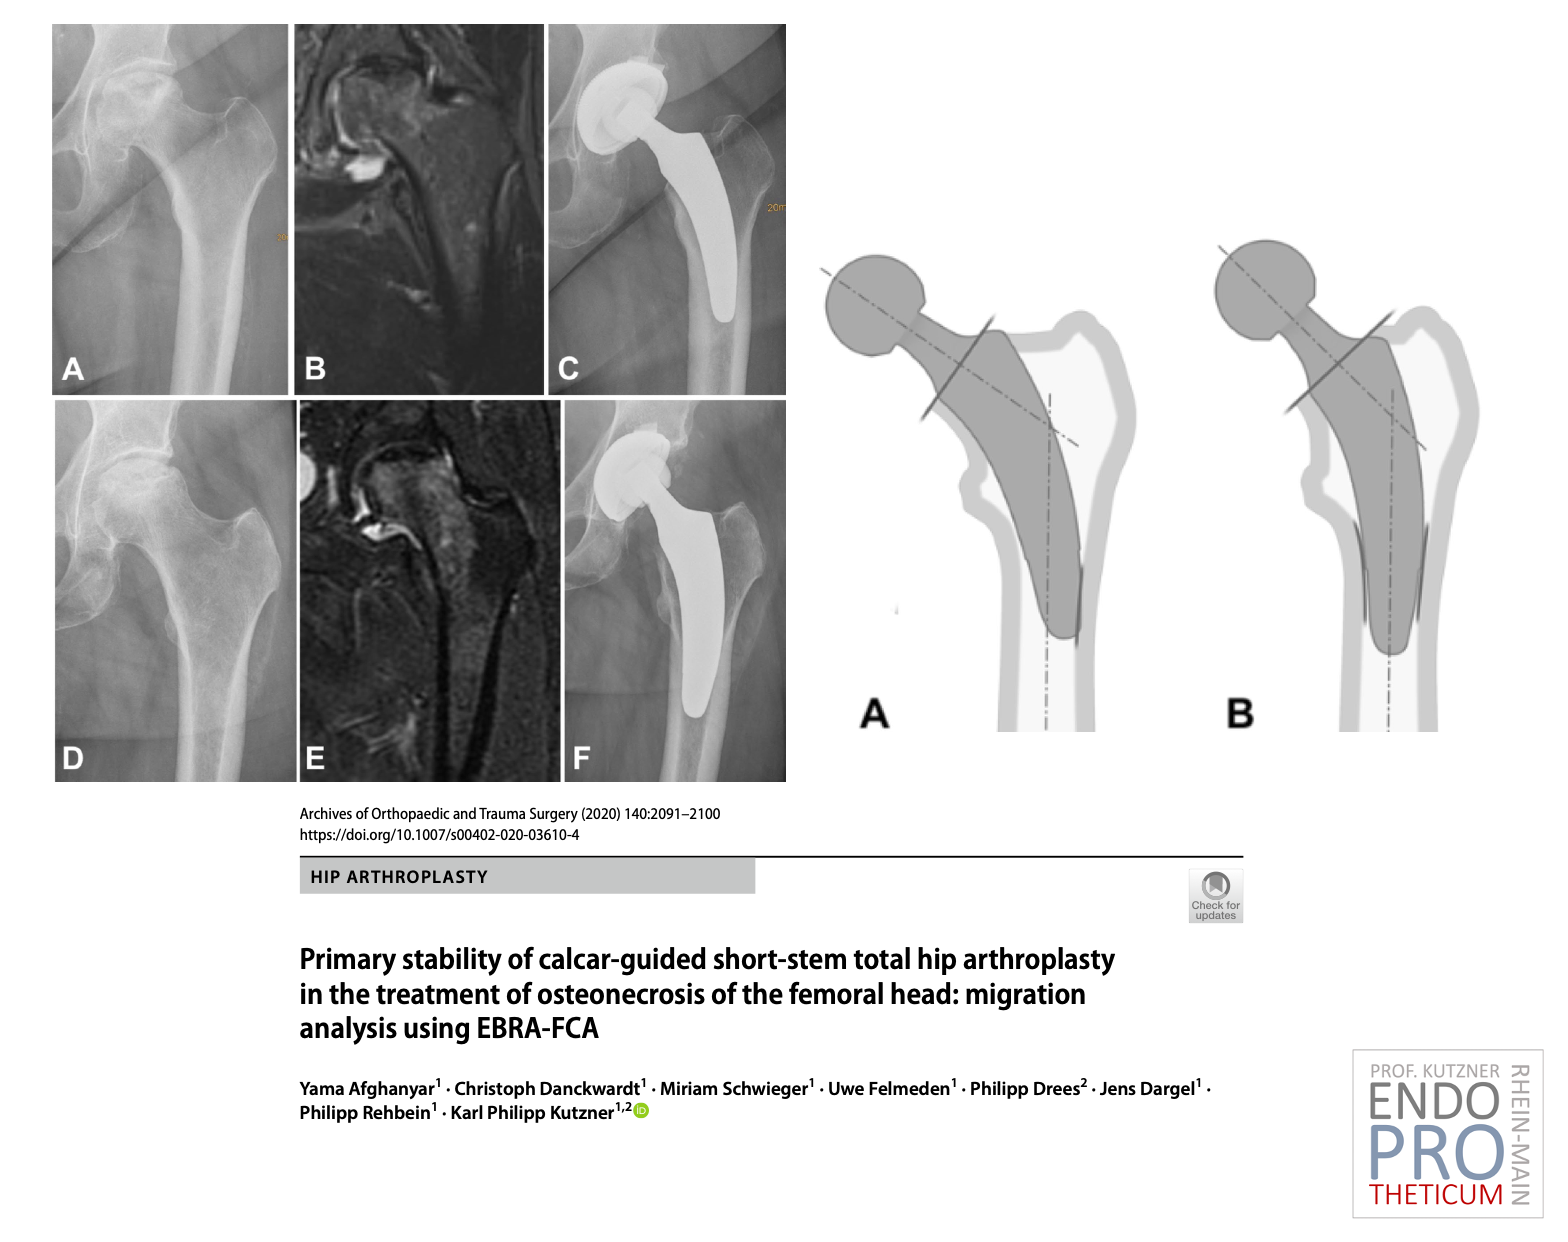

Le concept de tiges courtes modernes guidées par le calcar dans l'arthroplastie de la hanche vise à la reconstruction précise de la géométrie anatomique individuelle de la hanche. Une technique d'implantation douce pour les os et les tissus mous est utilisée en association avec une mise en charge physiologique dans la partie du fémur proche de l'articulation afin de préserver l'os à long terme.